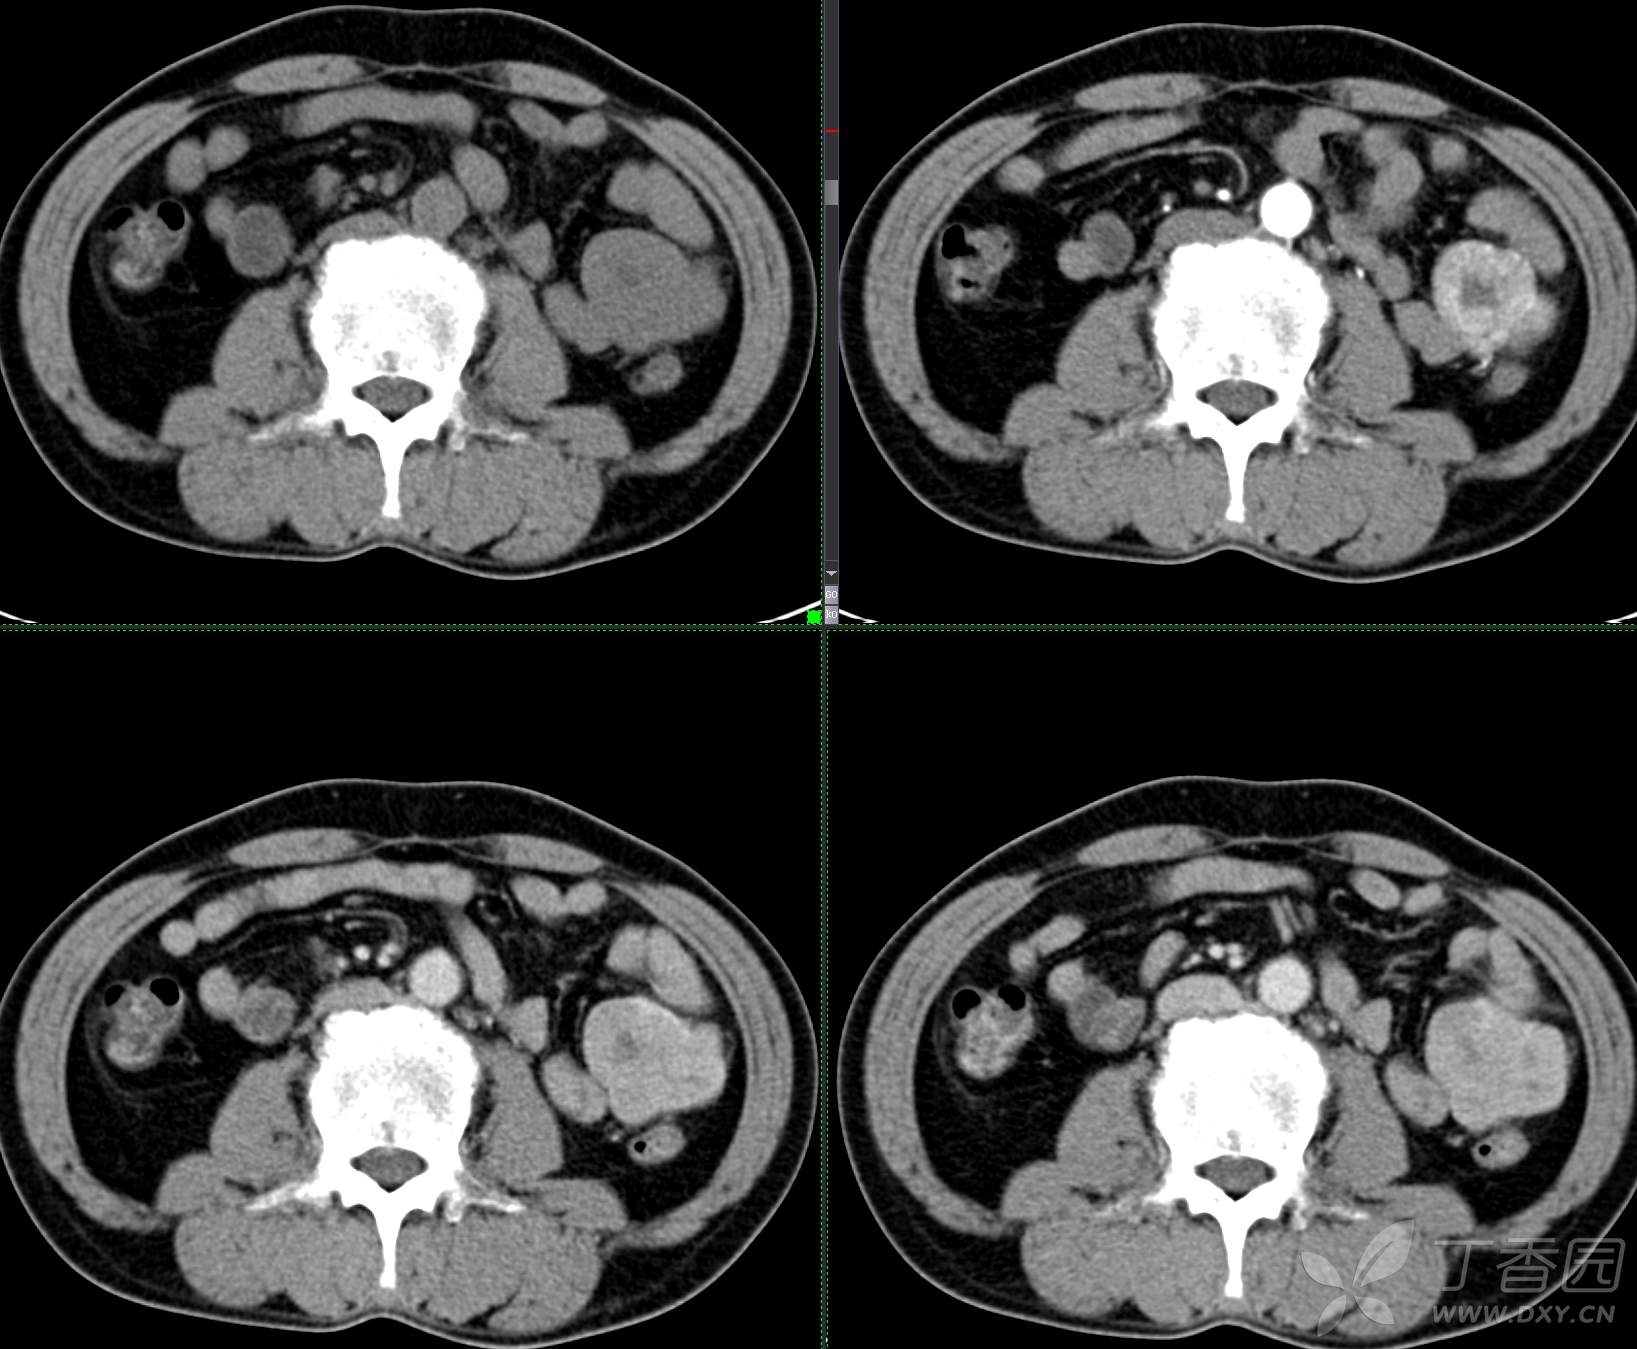

讨论:小肠病变,间质瘤?淋巴瘤?小肠腺癌?